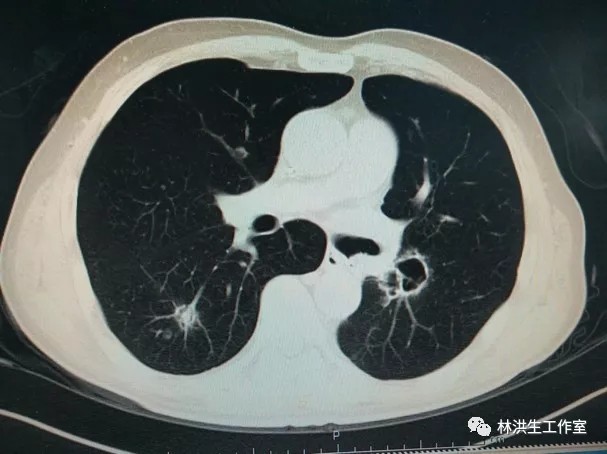

瘤体大小:中西医结病灶控制稳定

2017-10-21中药治疗后:双肺多发转移瘤大者增大至约2.6*2.3cm